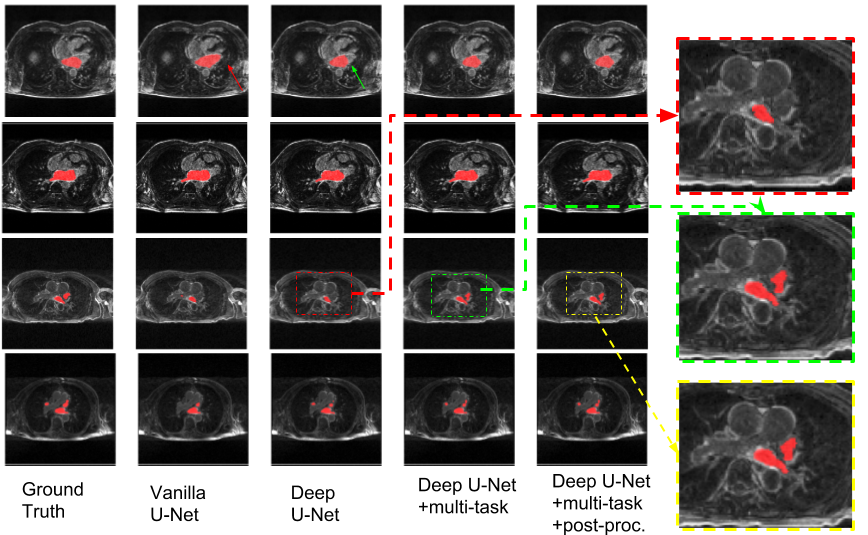

To show the advancement of our deep network with additional pooling/max-pooling layers, we compared our modified networks with the vanilla 2D U-Net. The results are shown in Table 2. It can be seen that the segmentation performance was greatly improved by increasing the depth of the network, especially in Mitral Valve(MV) planes. Our best results were achieved by using the multi-task Deep U-Net followed by post-processing, producing a Dice score of 0.901. From the visualization plots in Fig. 3, we could see that our multi-task U-Net is more robust than the other two with only one segmentation goal. One reason could be that by sharing features with segmentation and related pre/post ablation classification, the network is forced to learn better representation on images taken before the ablation treatment and those after the treatment, which could further improve segmentation performance. Fig. 4 showed that our model achieved high overlap ratio between our 3D segmentation result and the ground truth in different subjects. However, one significant failure mode can be observed around the region of pulmonary veins. One possible reason might be that the number and the length of pulmonary veins vary from person to person, making it too hard for the network to learn from limited cases.